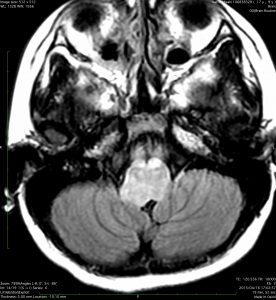

この脳幹部の橋グリオーマは小児に発生したものです。lateratityが強いと表現するのですが,左側に偏って存在しています。これは通常のびまん性橋膠腫では理解ができない画像ですから,生検術が必要かもしれません。でも病理確定診断がついたからといって,治療としてできることは50グレイくらいまでの局所放射線治療だけかもしれません。